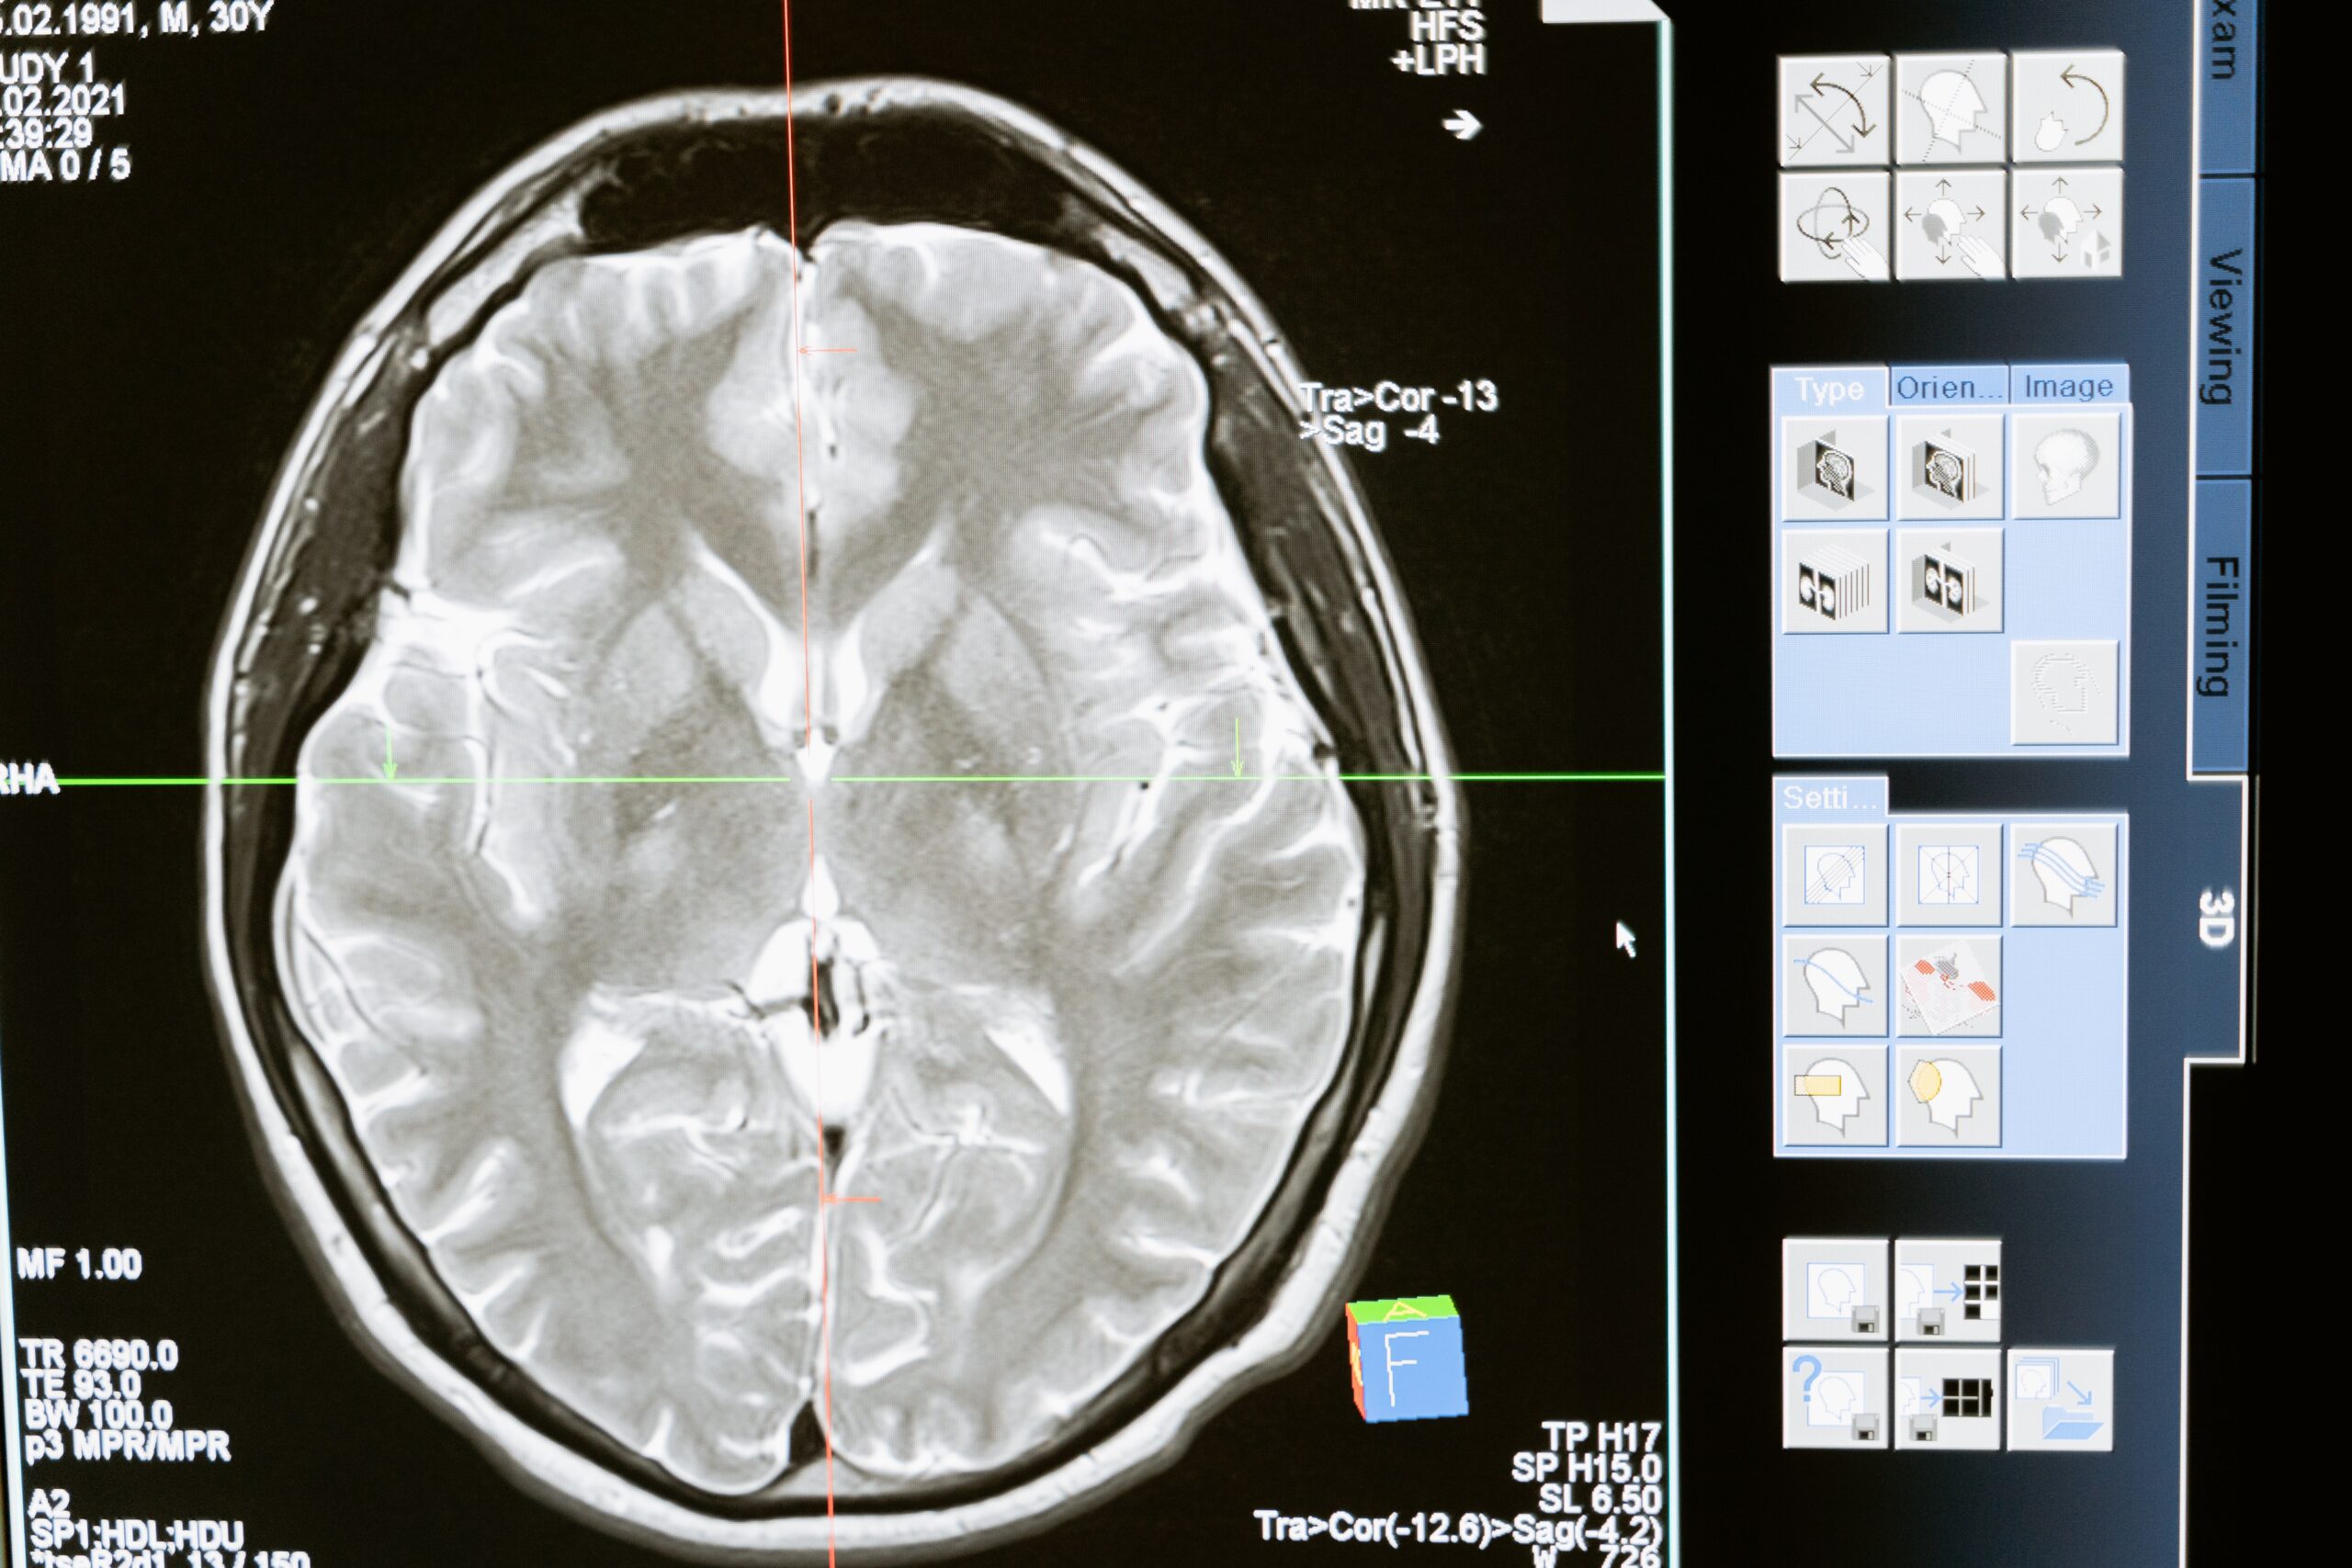

Traumatic brain injuries (TBI) occur when a person suffers a forceful external blow to the head which causes internal bleeding and bruising to the brain. Typically, TBIs occur as a result of a person’s brain colliding with their skull. This causes contusions on the brain and can lead to significant issues such as blood clots. TBIs are classified as either mild, moderate, or severe. The symptoms and deficits victims experience are typically debilitating and negatively affect their welfare. Qualifying for compensation can be complex. To qualify for compensation, victims should try to document, if possible, any symptoms or deficits they experience as a result of their TBI. Victims of TBIs may experience the following disturbances: